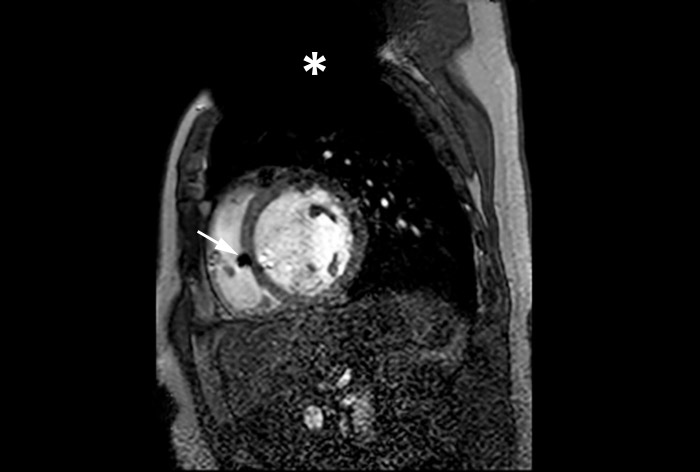

MRI of heart with MR Conditional ICD

A patient with an MR Conditional ICD and suspected myocarditis presented for MRI. This short axis view of the heart is created with an SSFP (steady state free precession) sequence on a Philips Achieva 1.5T system. The cardiac MRI exam reveals normal dimensions and regular function of the right and left ventricle. Note the ICD lead in the right ventricle (arrow) and the signal void in the left pectoral region, indicating the ICD-IPG (asterisk). Courtesy of Dr. Sommer.